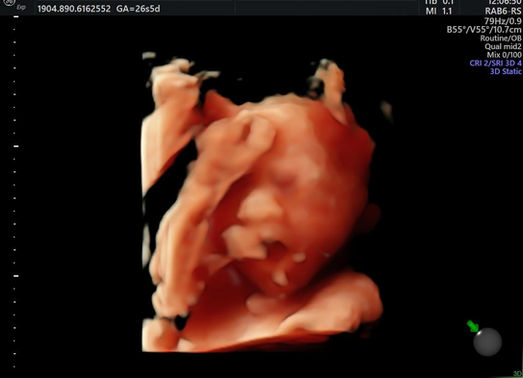

Dans ma pratique quotidienne, je réalise donc toutes les échographies obstétricales de dépistage au cours de la grossesse (datation, premier, deuxième et troisième trimestre, croissance avec dopplers, col de l’utérus), les échographies pré et post interruption volontaire de grossesse ou fausses couches, ainsi que les échographies pelviennes pour les contrôles de stérilet/DIU, les recherches d’endométriose ou autres motifs récurrents de consultation (douleurs pelviennes, métrorragies, bilan avant préservation de la fertilité etc... ).